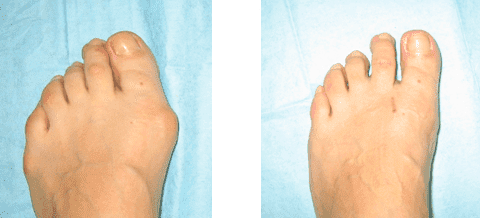

La mia gamba 1 mese dopo l'intervento

La mia gamba un mese dopo l'operazione

È così che ho camminato per l'ospedale. Era molto doloroso camminare...

Le mie gambe un mese dopo l'intervento

Le mie gambe 9 mesi dopo l'intervento

Ecco come sono le mie gambe un anno dopo aver usato Artrosteel